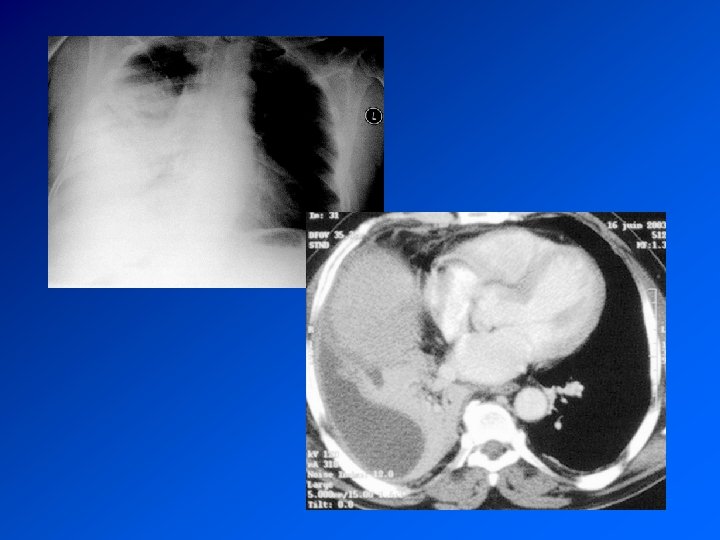

Mésothéliome pleural Cancer primitif de la plèvre Principal facteur de risque (retrouvé dans > 80% des méso): exposition à l’AMIANTE CDD : AEG douleur, syndrome pleural. Surveillance d’un sujet exposé Radio : pleurésie. Epaississement tumoral nodulaire de la plèvre. Extension extrathoracique rare mais possible Evolution défavorable. Survie moyenne 9 à 12 mois. Traitement décevant : chimiothérapie. Radiothérapie sur orifices biopsies et drainage Symphise pleurale

Enquête diagnostique Histoire de la maladie : recherche une maladie déjà connue, une exposition à un toxique professionnel, la prise de médicaments Examen clinique retrouve le syndrome pleural. Recherche de signes d’autres maladies associée Radio de thorax : fait le diagnostic TDM Thorax : précise les images Ponction pleurale oriente en fonction de la cytologie